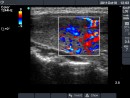

Ultrasonography: Both lobes were enlarged, moderately hypoechogenic, inhomogeneous and displayed increased vascularization.

2. Note the relation between volume, echogenicity, vascularization and hormone levels.